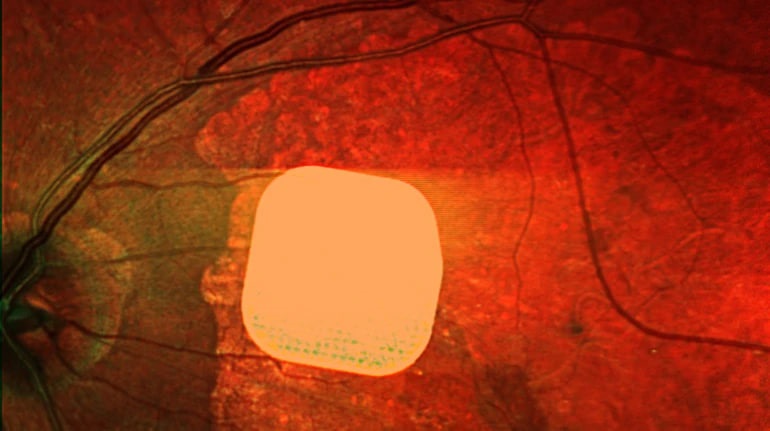

Британські лікарі з Moorfields Eye Hospital спільно з європейськими колегами розробили тонкий електронний імплант Prima, який допомагає пацієнтам із віковою сліпотою, спричиненою макулодистрофією, частково відновити зір. Цей мікрочип встановлюють під сітківку ока пацієнта під час короткої операції. Йому також надають систему окулярів доповненої реальності, яка допомагає передавати зображення на мікрочип та активувати клітини сітківки. У дослідженні взяли участь 38 пацієнтів із макулодистрофією, і 84% з них після адаптації знову змогли розрізняти літери, цифри та слова. Лікарі вважають, що ця технологія відкриває нові можливості для людей із важкими зоровими проблемами, допомагаючи покращити їхню якість життя.